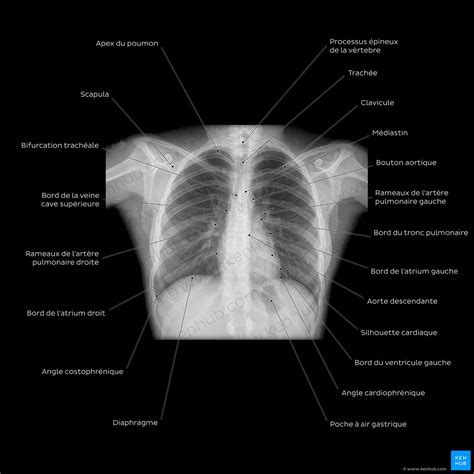

La radiographie thoracique, en particulier l'incidence de face, permet d'évaluer la taille et la forme du cœur, ainsi que les contours des gros vaisseaux qui l'entourent. Une dilatation des cavités cardiaques est l'une des causes principales de modifications de la silhouette cardiaque. Cette dilatation se traduit souvent par une cardiomégalie, définie par un index cardio-thoracique supérieur à 0,5, une mesure qui compare la largeur maximale du cœur à la largeur maximale du thorax.

L'analyse détaillée des différents arcs de la silhouette cardiaque permet de localiser précisément les anomalies. Par exemple, une dilatation de l'oreillette droite se manifeste par un élargissement de l'arc inférieur droit, lui conférant un aspect plus convexe. De même, une dilatation du ventricule droit entraîne une saillie de l'arc inférieur gauche, lui donnant un aspect arrondi et surélevé au niveau de la pointe. Une dilatation importante de l'oreillette gauche peut provoquer un aspect de double contour de l'arc inférieur droit et, de manière significative pour notre sujet, une saillie de l'arc moyen gauche. Enfin, une dilatation du ventricule gauche se traduit par une saillie de l'arc inférieur gauche qui tend à se rapprocher de la partie latérale du thorax.

L'arc moyen gauche, dans une radiographie thoracique normale, est principalement formé par la crosse aortique et l'artère pulmonaire. Lorsque cet arc présente une saillie anormale, cela peut indiquer plusieurs pathologies. La dilatation de l'artère pulmonaire est une cause fréquente de cette saillie. L'artère pulmonaire est le vaisseau qui transporte le sang désoxygéné du ventricule droit vers les poumons. Sa dilatation peut être le signe d'une hypertension pulmonaire, une condition où la pression sanguine dans les artères pulmonaires est anormalement élevée.

Le médiastin, la région centrale du thorax située entre les deux poumons, abrite des structures vitales telles que le cœur, l'aorte, la trachée, l'œsophage et les ganglions lymphatiques. Les contours médiastinaux, visibles sur les radiographies de thorax, fournissent des informations précieuses sur l'état de ces organes. À droite, l'arc supérieur correspond au tronc veineux brachio-céphalique droit, l'arc moyen à la veine cave supérieure, et l'arc inférieur à l'atrium droit et, dans une moindre mesure, à la veine cave inférieure. Le hile pulmonaire gauche est physiologiquement situé légèrement plus haut que le hile droit.

L'interprétation d'une radiographie thoracique implique l'analyse des différents éléments anatomiques, y compris les structures médiastinales et les contours cardiaques. Le signe de la silhouette est un outil précieux pour localiser une opacité en déterminant si elle est en contact avec une structure de densité similaire, rendant leurs contours indistincts.